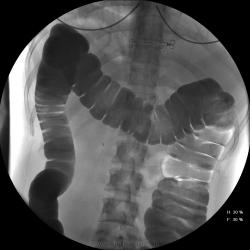

Девушка, 27 лет, жалуется на периодические боли в правой подвздошной области, области паха справа. Во время этого идет нарушение стула - то слабит, то несколько дней не может ходить в туалет, вздутие кишечника. Жалобы несколько лет . Обследованна кем только можно. Хирург посоветовал ирригоскопию. Работа достаточно нервная. До первого случая данных проблем , за неделю, проходила сан лечение в пансионате ( для поднятия общего иммунитета - так говорит), был курс клизм с травами - сама думает, что это не связанно.

В целом -не вижу, к чему придраться, хоть и тонус низковат. Что это? В проекции левого мечеточника. Причем цепочка тенюшек тянется под диафрагму занчительно выше проеции почки?

Цепочка тенюшек - это наша "гордость)" следы от контраста после гистеросальпингоскопии. чтоб вымыть ,надо разбирать стол , а это только с представителем сименса. вот так.) а правые отделы толстой кишки на расширены? я кроме лополнительной петли сигмы сам ничего не вижу. несколько настораживает некоторое расширение правых отделов кишки- может за счет запоров, которые случаются у девушки? не хочется что то пропустить.

Считаю, данных за долихосигму нет.

Признак долихосигмы - это наличие т.н. симптома "трехстволки", есть это - есть и долихосигма. В данном случае такой вариант имеет место быть.